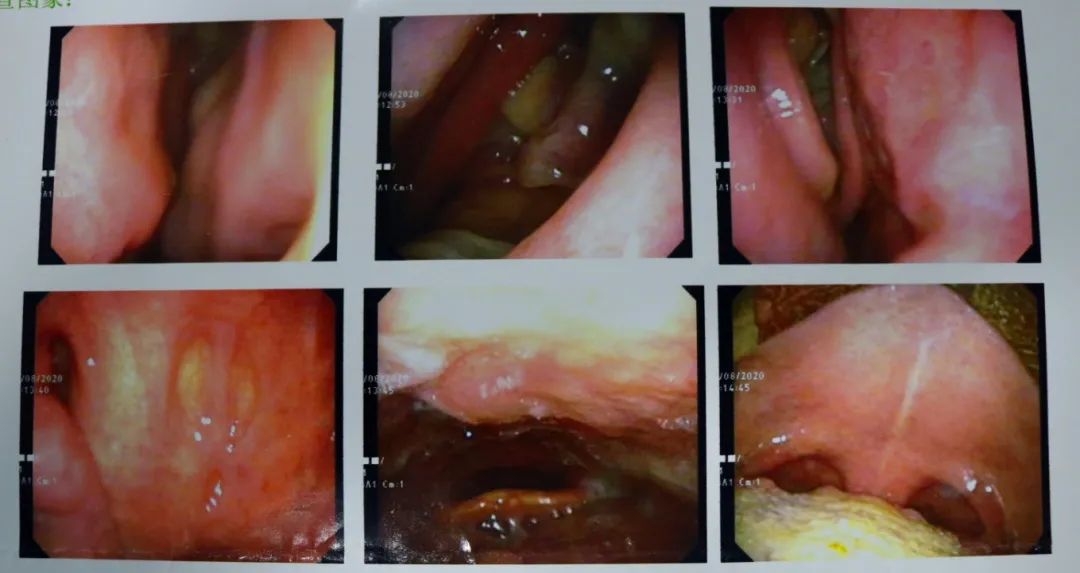

经影像学检查发现,患者双侧上颌窦窦腔内见多发团状高密度影。结合患者临床表现,可以确诊刘先生患有鼻窦炎。根据患者本人的意愿和身体状况,朱主任决定先采用我院的“鼻五联疗法”进行保守治疗。